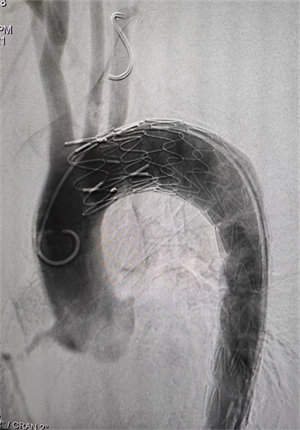

经过胸痛中心绿色通道排除心梗考虑夹层可能,经口服降压、镇痛稍好转后第一时间行急诊胸腹主动脉CTA,确诊为胸主动脉夹层,夹层从左侧锁骨下一直撕到左侧髂总动脉,真腔近乎只有假腔的1/4,病情十分凶险!急诊入住我院普外二科进一步监护治疗,治疗期间由于血压难以控制,夹层破裂风险进一步增高,需急诊手术进一步干预。经过科内讨论建议急诊行胸主动脉介入治疗。最终在介入中心、麻醉科、手术室的密切配合下,于2月1日下午在介入中心、麻醉科、手术室的密切配合以及上级专家的指导下完成了胸主动脉覆膜支架腔内隔绝术,术后造影可见左侧锁骨下动脉显影良好且无内漏,手术效果满意!